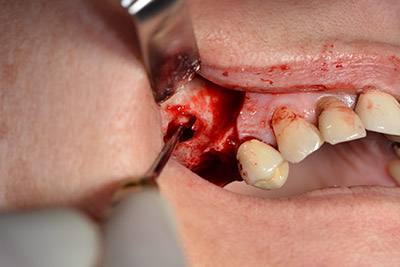

The classic incision (crestal, buccal relief) and the preparation of the mucoperiosteal flap enabled a good overview.

The fenestration was prepared at 35,000 rpm and then the nasal mucosa were prepared in the cranial direction (Fig. 13 to 14).